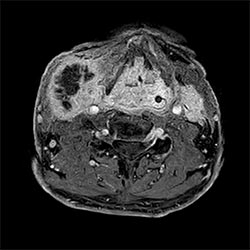

In a society where reimbursements are declining and chronic conditions lead to increased MR procedures and longer waiting times, there is ever increasing pressure on the radiology department. Today, further attempts to accelerate, compromise image quality or are limited to a narrow range of scans. Therefore, to meet the increased demand for productivity, a technology break-through in acceleration is still required. Leveraging our long standing leadership position in speed (i.e. SENSE), Philips brings compressed SENSE, a breakthrough in productivity.

Learn more about the main principles of Compressed SENSE and how it introduces a paradigm shift in productivity, how Compressed SENSE was designed around image quality, and how it advances productivity for clinical MR imaging.